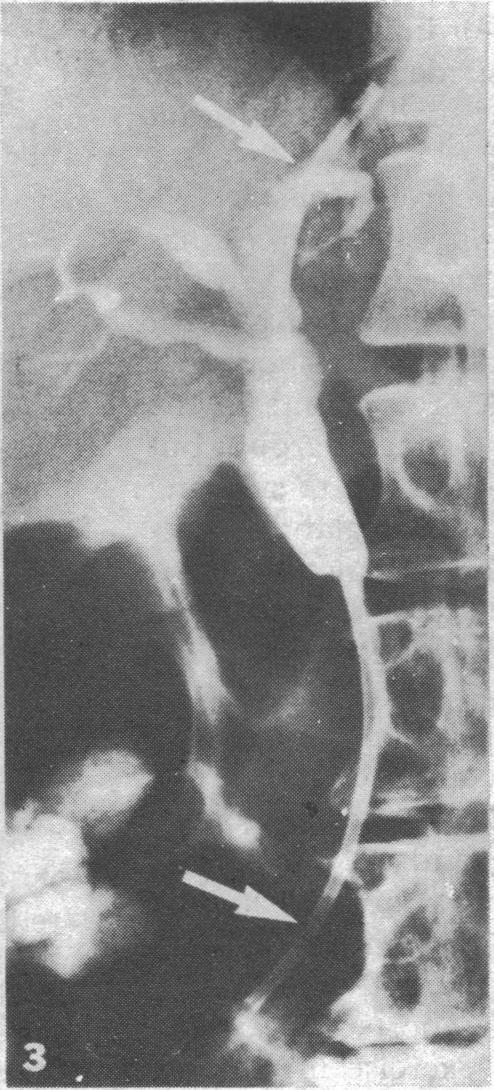

Interest is increasing in non-operative methods of relieving malignant obstruction of the bile duct, and drainage tubes and prostheses may be placed in the bile duct via the percutaneous transhepatic route. Two cases are described, however, in which a duodenoscope was used and the approach was via the papilla of Vater. This method allows temporary or permanent drainage tubes to be placed through malignant strictures. This endoscopic approach is less invasive and should be safer than that by the transhepatic route; furthermore, removing and replacing a blocked endoprosthesis should be easier. Further study is needed, as the procedure is technically more difficult and its role in managing biliary strictures has yet to be defined.

缓解恶性胆管梗阻的非手术方法越来越受到关注,引流管和假体可通过经皮肝穿刺途径放置在胆管中。然而,本文描述了两例使用十二指肠镜并经十二指肠乳头入路的病例。这种方法允许通过恶性狭窄放置临时或永久性引流管。这种内镜入路的侵入性较小,应该比经肝途径更安全;此外,取出和更换堵塞的内置假体应该更容易。由于该手术在技术上更困难,其在处理胆管狭窄中的作用尚未明确,因此需要进一步研究。